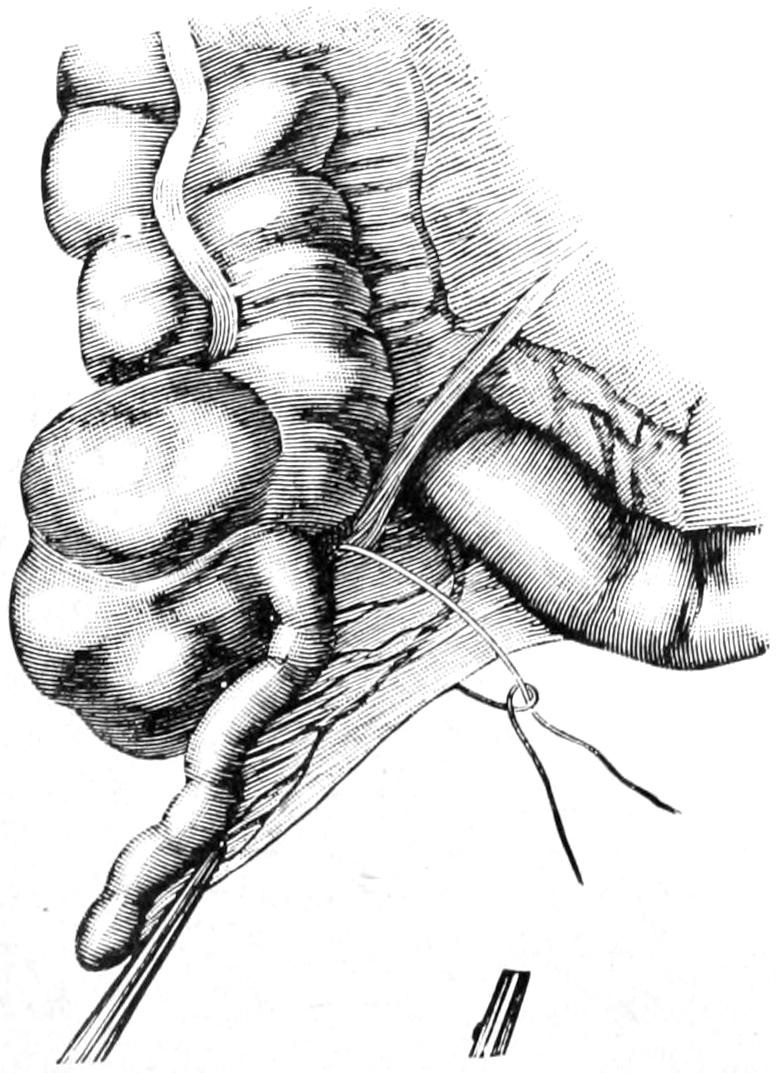

CHAPTER XLVIII.

THE SMALL INTESTINES 822